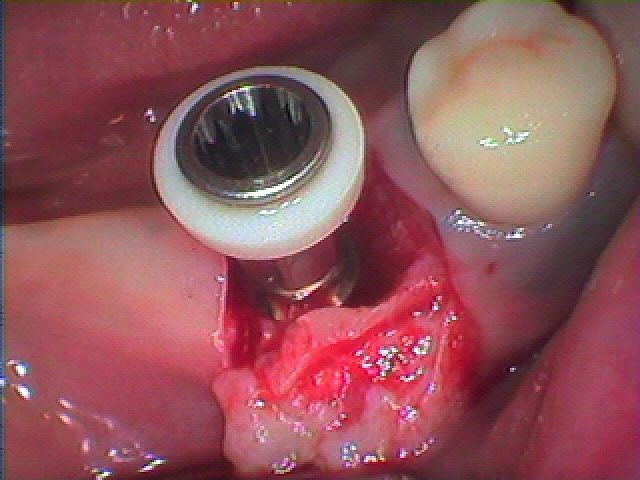

インプラント埋入時になります